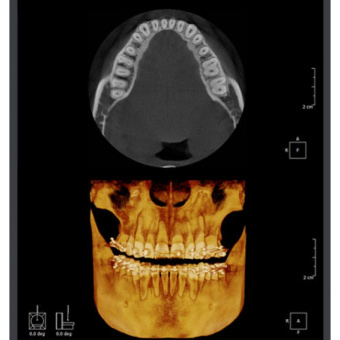

Ортопантомограф RAYSCAN является передовым диагностическим оборудованием, в котором применяются 2 сенсора: высококачественный плоский сенсор HAMAMATSU (Япония) для панорамной съёмки и отдельный сканирующий сенсор, которые обеспечивают чёткое изображение с первого раза (даже волос и мягких тканей), последний имеет различные режимы сканирования.

Передовое программное обеспечение SMARTDent оснащено простым, понятным для пользователя графическим интерфейсом для анализа двухмерных изображений.

Программа SMARTDent позволяет вам просматривать вплоть до 4 окон с изображениями, что облегчает сравнение снимков